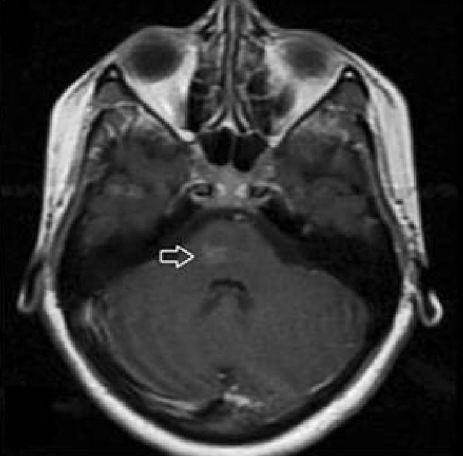

病例14

男性,49岁,发热5天,后出现癫痫发作多次,发作后持续意识障碍。查体颈部强直。入院后脑脊液白细胞9600*10^6/L,糖1.1mmol/L,蛋白1.35g/L,多核比例90%。发病前期CT正常,发病1月后复查MRI如下:

答案:化脓性脑膜炎,远隔性小脑出血。

本例患者有一定难度,患者脑脊液化验结果支持是化脓性脑膜炎。但是患者的小脑有出血,好多老师不了解其中的关系。这是远隔性小脑出血(Remote cerebellar hemorrhage)。远隔性小脑岀血可发生在多种神经外科手术后,如动脉瘤夹闭手术、颞叶切 除、肿瘤切除术、颅内血肿引流术后,也可在椎管手术、腰椎穿刺后发生,准确发生率尚不清楚,相关文献报道为0.8%~5.0%。目前多数学者认为RCH发生机制为颅内压变化学说,即颅内压骤然下降或升高,可使脑组织移位,脑血管牵拉撕裂。出血可能是单侧或双侧,多为表浅实质出血,典型CT表现为小脑表面沟弧线状高密度影,此表现称为“斑马征”。